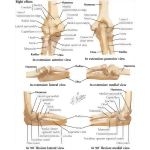

Bones of Elbow

Bones of Elbow

Labeled - Cleland Ortho Clinical Exam 1E